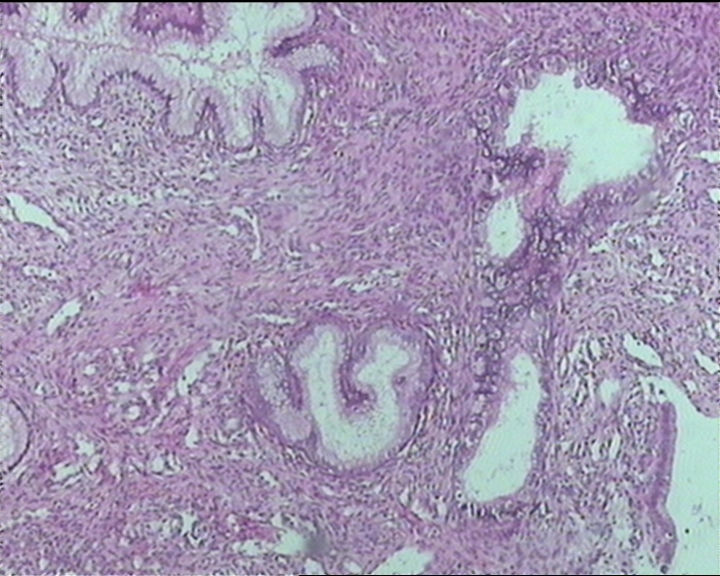

54岁女性,临床“宫颈息肉”送检;巨检:组织一块1。5*1CM,灰红。

Sternberg病理学上诊断宫颈原位腺癌的标准是腺体的上皮去粘液分化,呈乳头状或筛网状增生,核分裂易见,这例显然达不到此标准。此例还是归入到腺上皮不典型增生为好。

It is benign. Benign endocervical polyp with tubal metaplasia.

输卵管粘膜化生

细胞及腺体均有异形,图6、11、16象有纤维间质反应,考虑高级别上皮内瘤变/原位癌,腺癌不能除外。